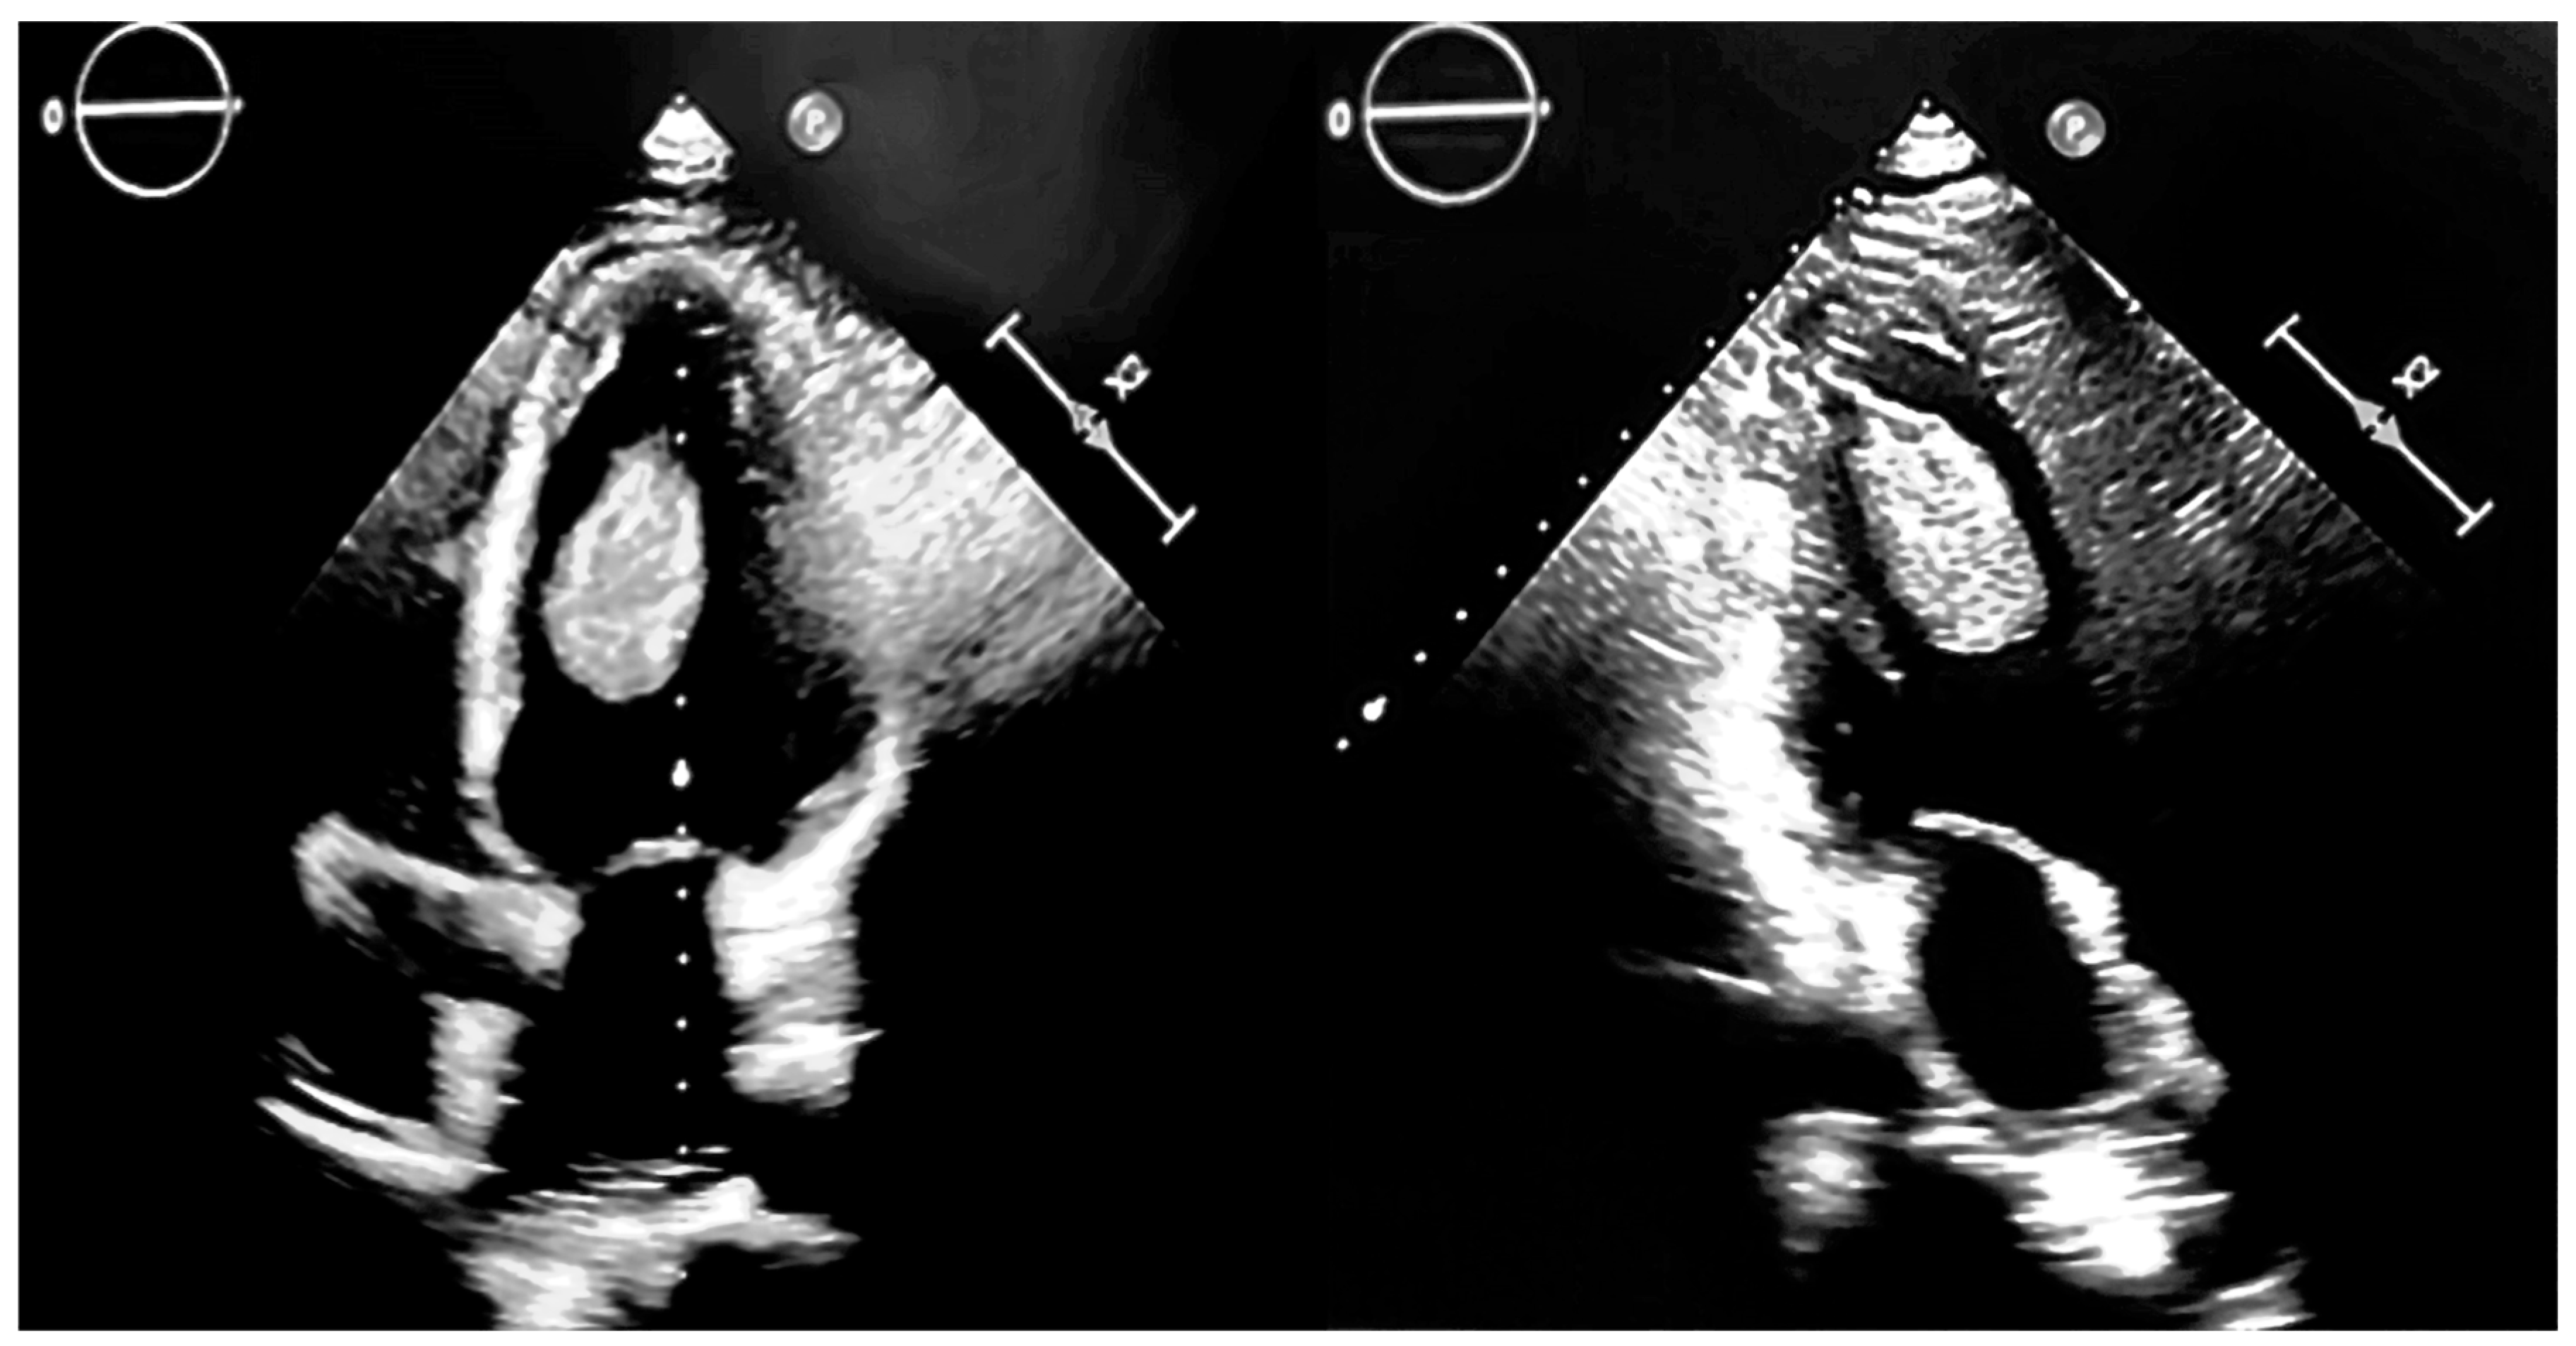

Particularities of a Cardiac Amorphous Left Ventricular Tumor in a Patient with Coronary Artery Disease—Diagnostic and Therapeutic Challenges: A Case Report and Literature Review

2. Case Presentation